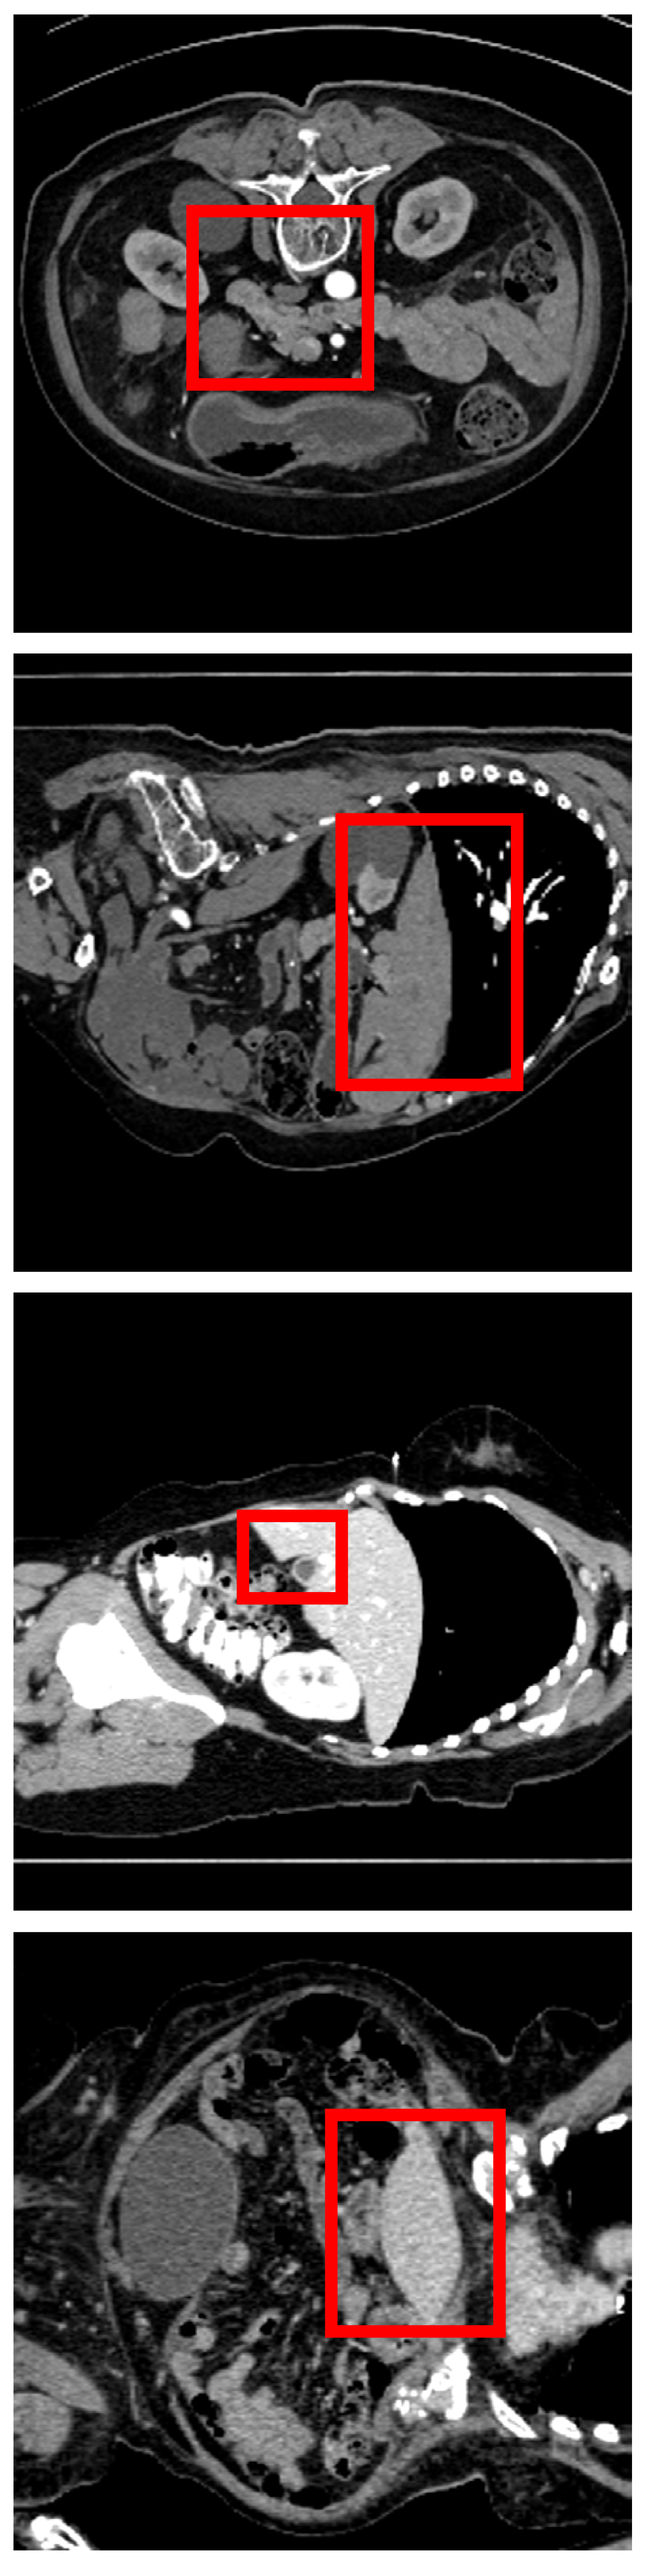

Refer to caption

(a) Image

(b) A&D [41]

(c) GA [32]

(d) TAK

(e) GT

Figure 4: Some qualitative segmentation results of our TAK and some state-of-the-art methods on Amos dataset [18] (first two rows) and Synapse dataset [21] (last two rows).

Following GA [32], we evaluate our approach against six state-of-the-art (SOTA) semi-supervised segmentation methods – UA-MT [46], CPS [10], DeSCO [6], DePL [42], Co-BioNet [31], and MagicNet [8] – as well as eight advanced SOTA techniques for handling class imbalance: Adsh [14], CReST [44], SimiS [9], Basak et al. [3], CLD [25], DHC [40], A&D [41], and GA [32]. We define classes with a voxel proportion of less than 5% of all organ categories (excluding the background) as small classes and those exceeding 5% as large classes. The specific voxel proportions of different organs can be found in the supplementary. In AMOS dataset [18], large classes include liver (Li), stomach (St), spleen (Sp), left kidney (LK), right kidney (RK) , and bladder (Bl); small classes include the rest. In Synapse dataset [21], large classes include Li, St, Sp, LK and RK; the others are small classes. Compared to various state-of-the-art methods, our proposed TAK achieves significant improvements. Some qualitative results are shown in Fig. 4. Fig. 6 compares the computational complexity and model size of different methods, showing TAK’s significant improvements with similar FLOPs and parameters as GA [32]. The results using the ASD metric and is provided in the supplementary.